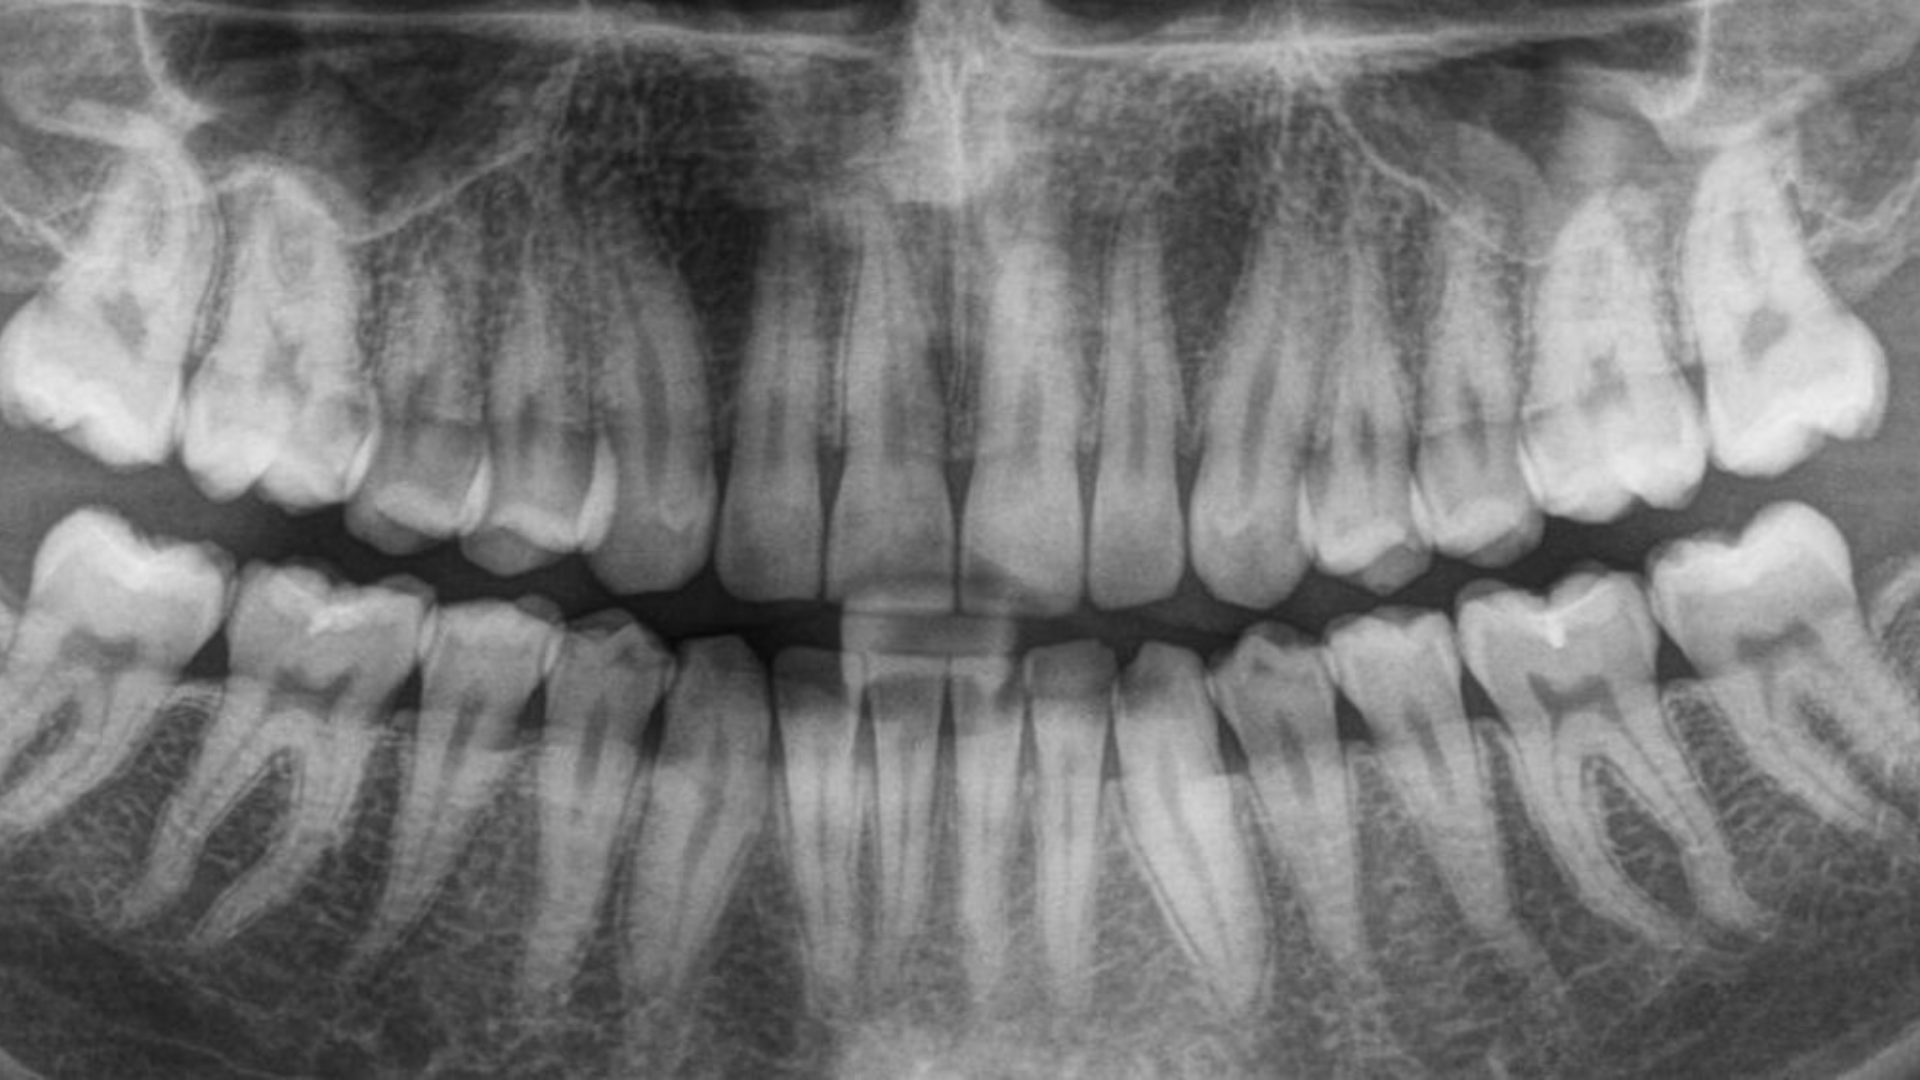

• Advanced digital imaging

• Digital imaging